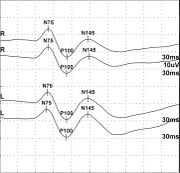

| 11:24, 1 April 2023 | Potenziale evocato acustico.jpeg (file) |  |

100 KB | 1 | |